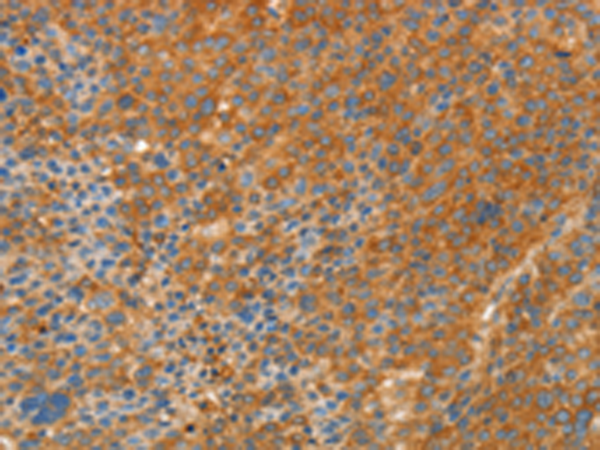

分类: 科研抗体货号: P07128别名: GAF; FGF-9; SYNS3; HBFG-9; HBGF-9应用: WB,IHC反应种属: Human, Mouse, Rat